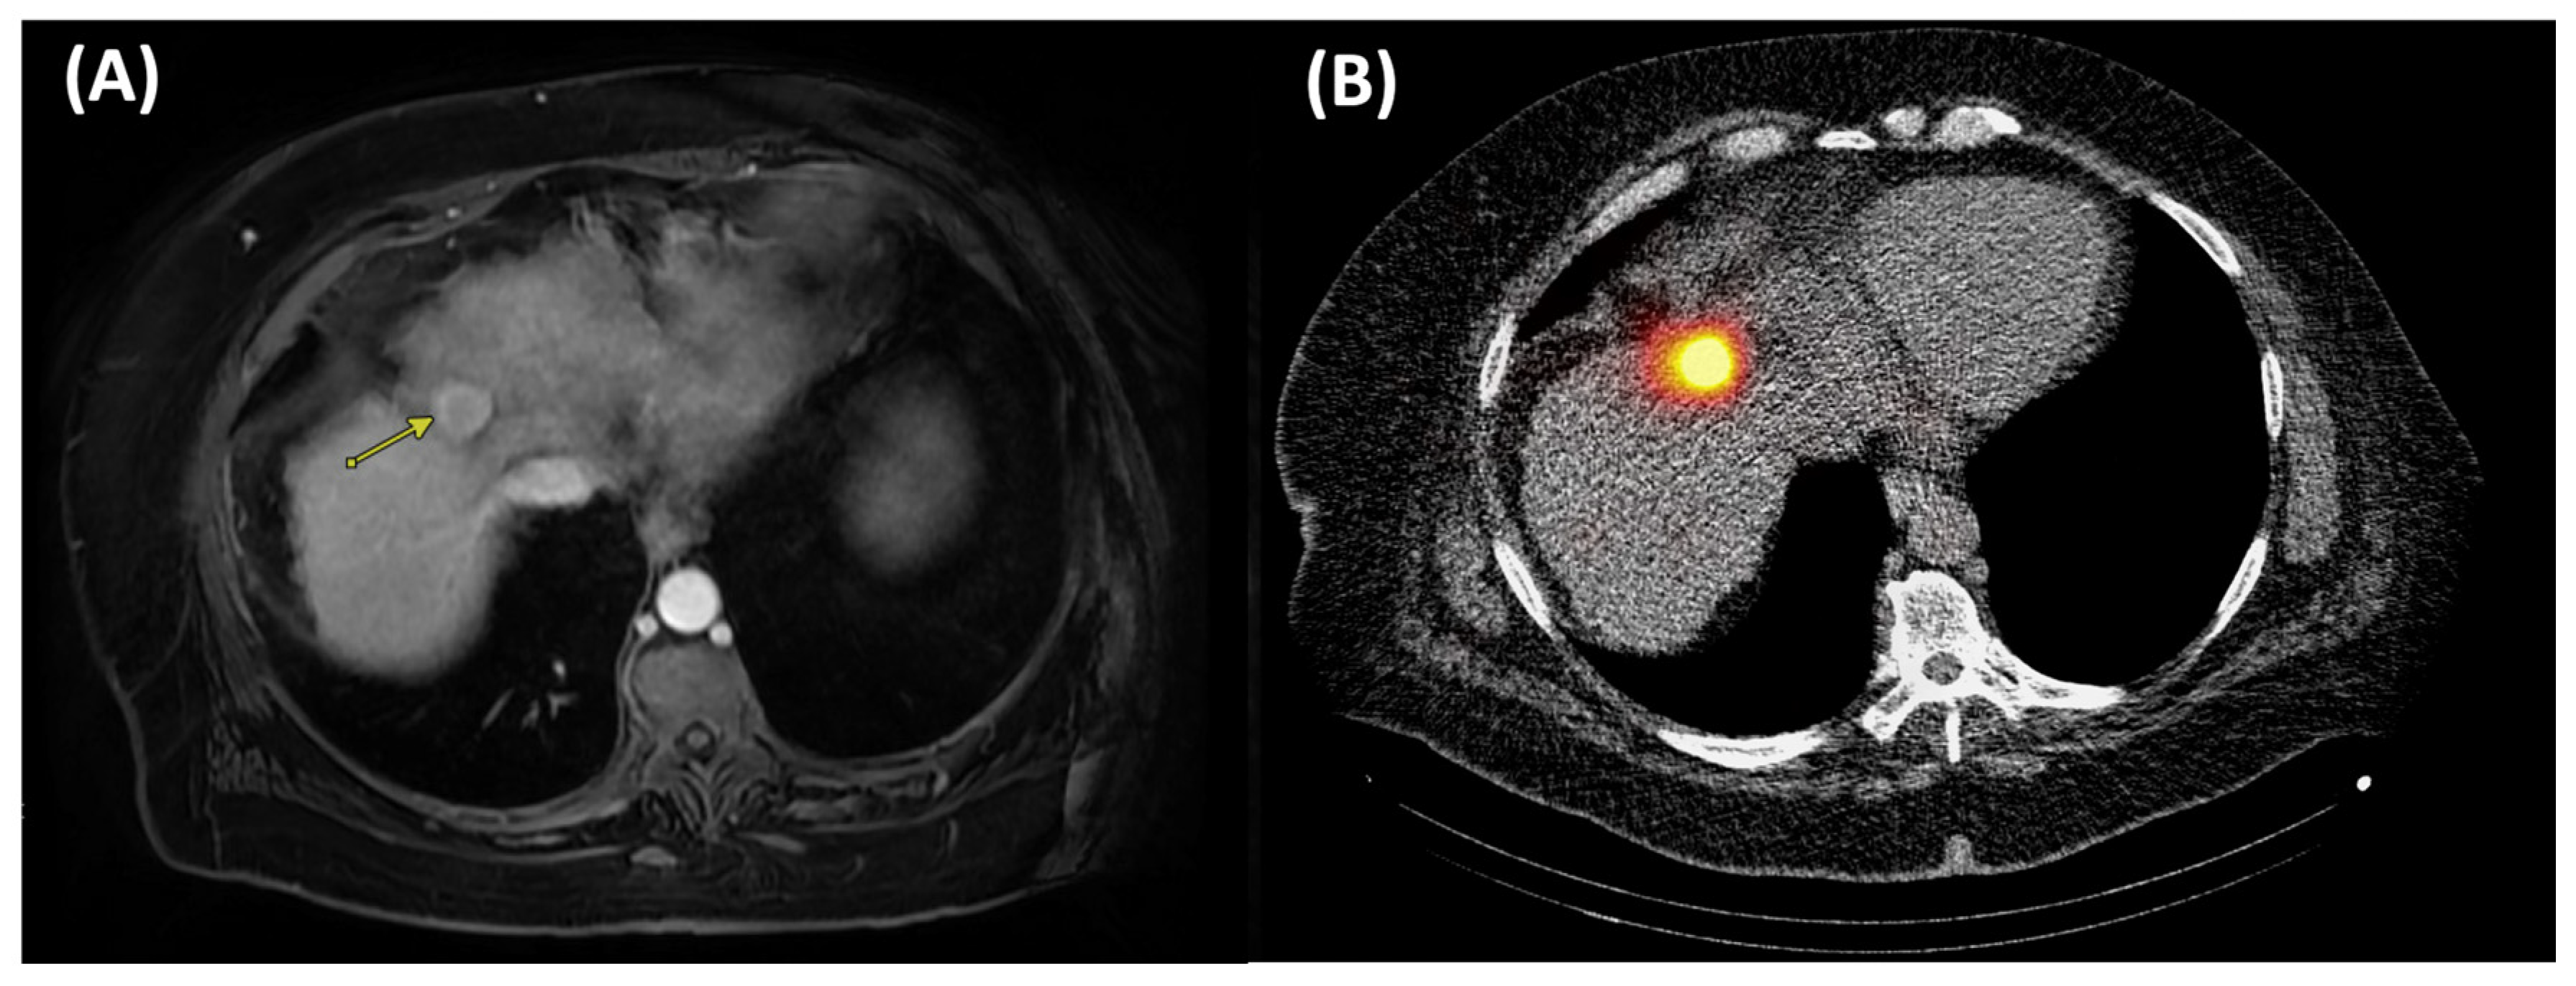

4.1. Trans-Arterial Radioembolization

4.2. External Beam Radiotherapy